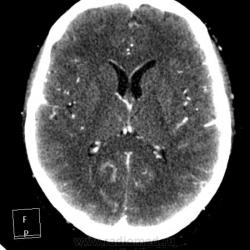

Мужчине 67 лет. У меня нет четкого мнения об изменении в правой затылочной доле. Ваше мнение?

"Непонятная штука в затылочной доле"-вероятнее артерио-венозная мальформация.Гиподенсная зона,прилежащая к ней-отдаленное последствие кровоизлиния из АВМ.

Может кавернома.

Склоняюсь к АВМ, прослеживается приводящий и отводящий сосуды. Не совсем понятно понижение плотности между сосудистыми петлями (может, коллега gar70 прав/а). Рекомендовала МРТ после выписки из сосудистого отделения (у нас такие вещи, что бы из сосудистых аномалий ни было, не оперируют).